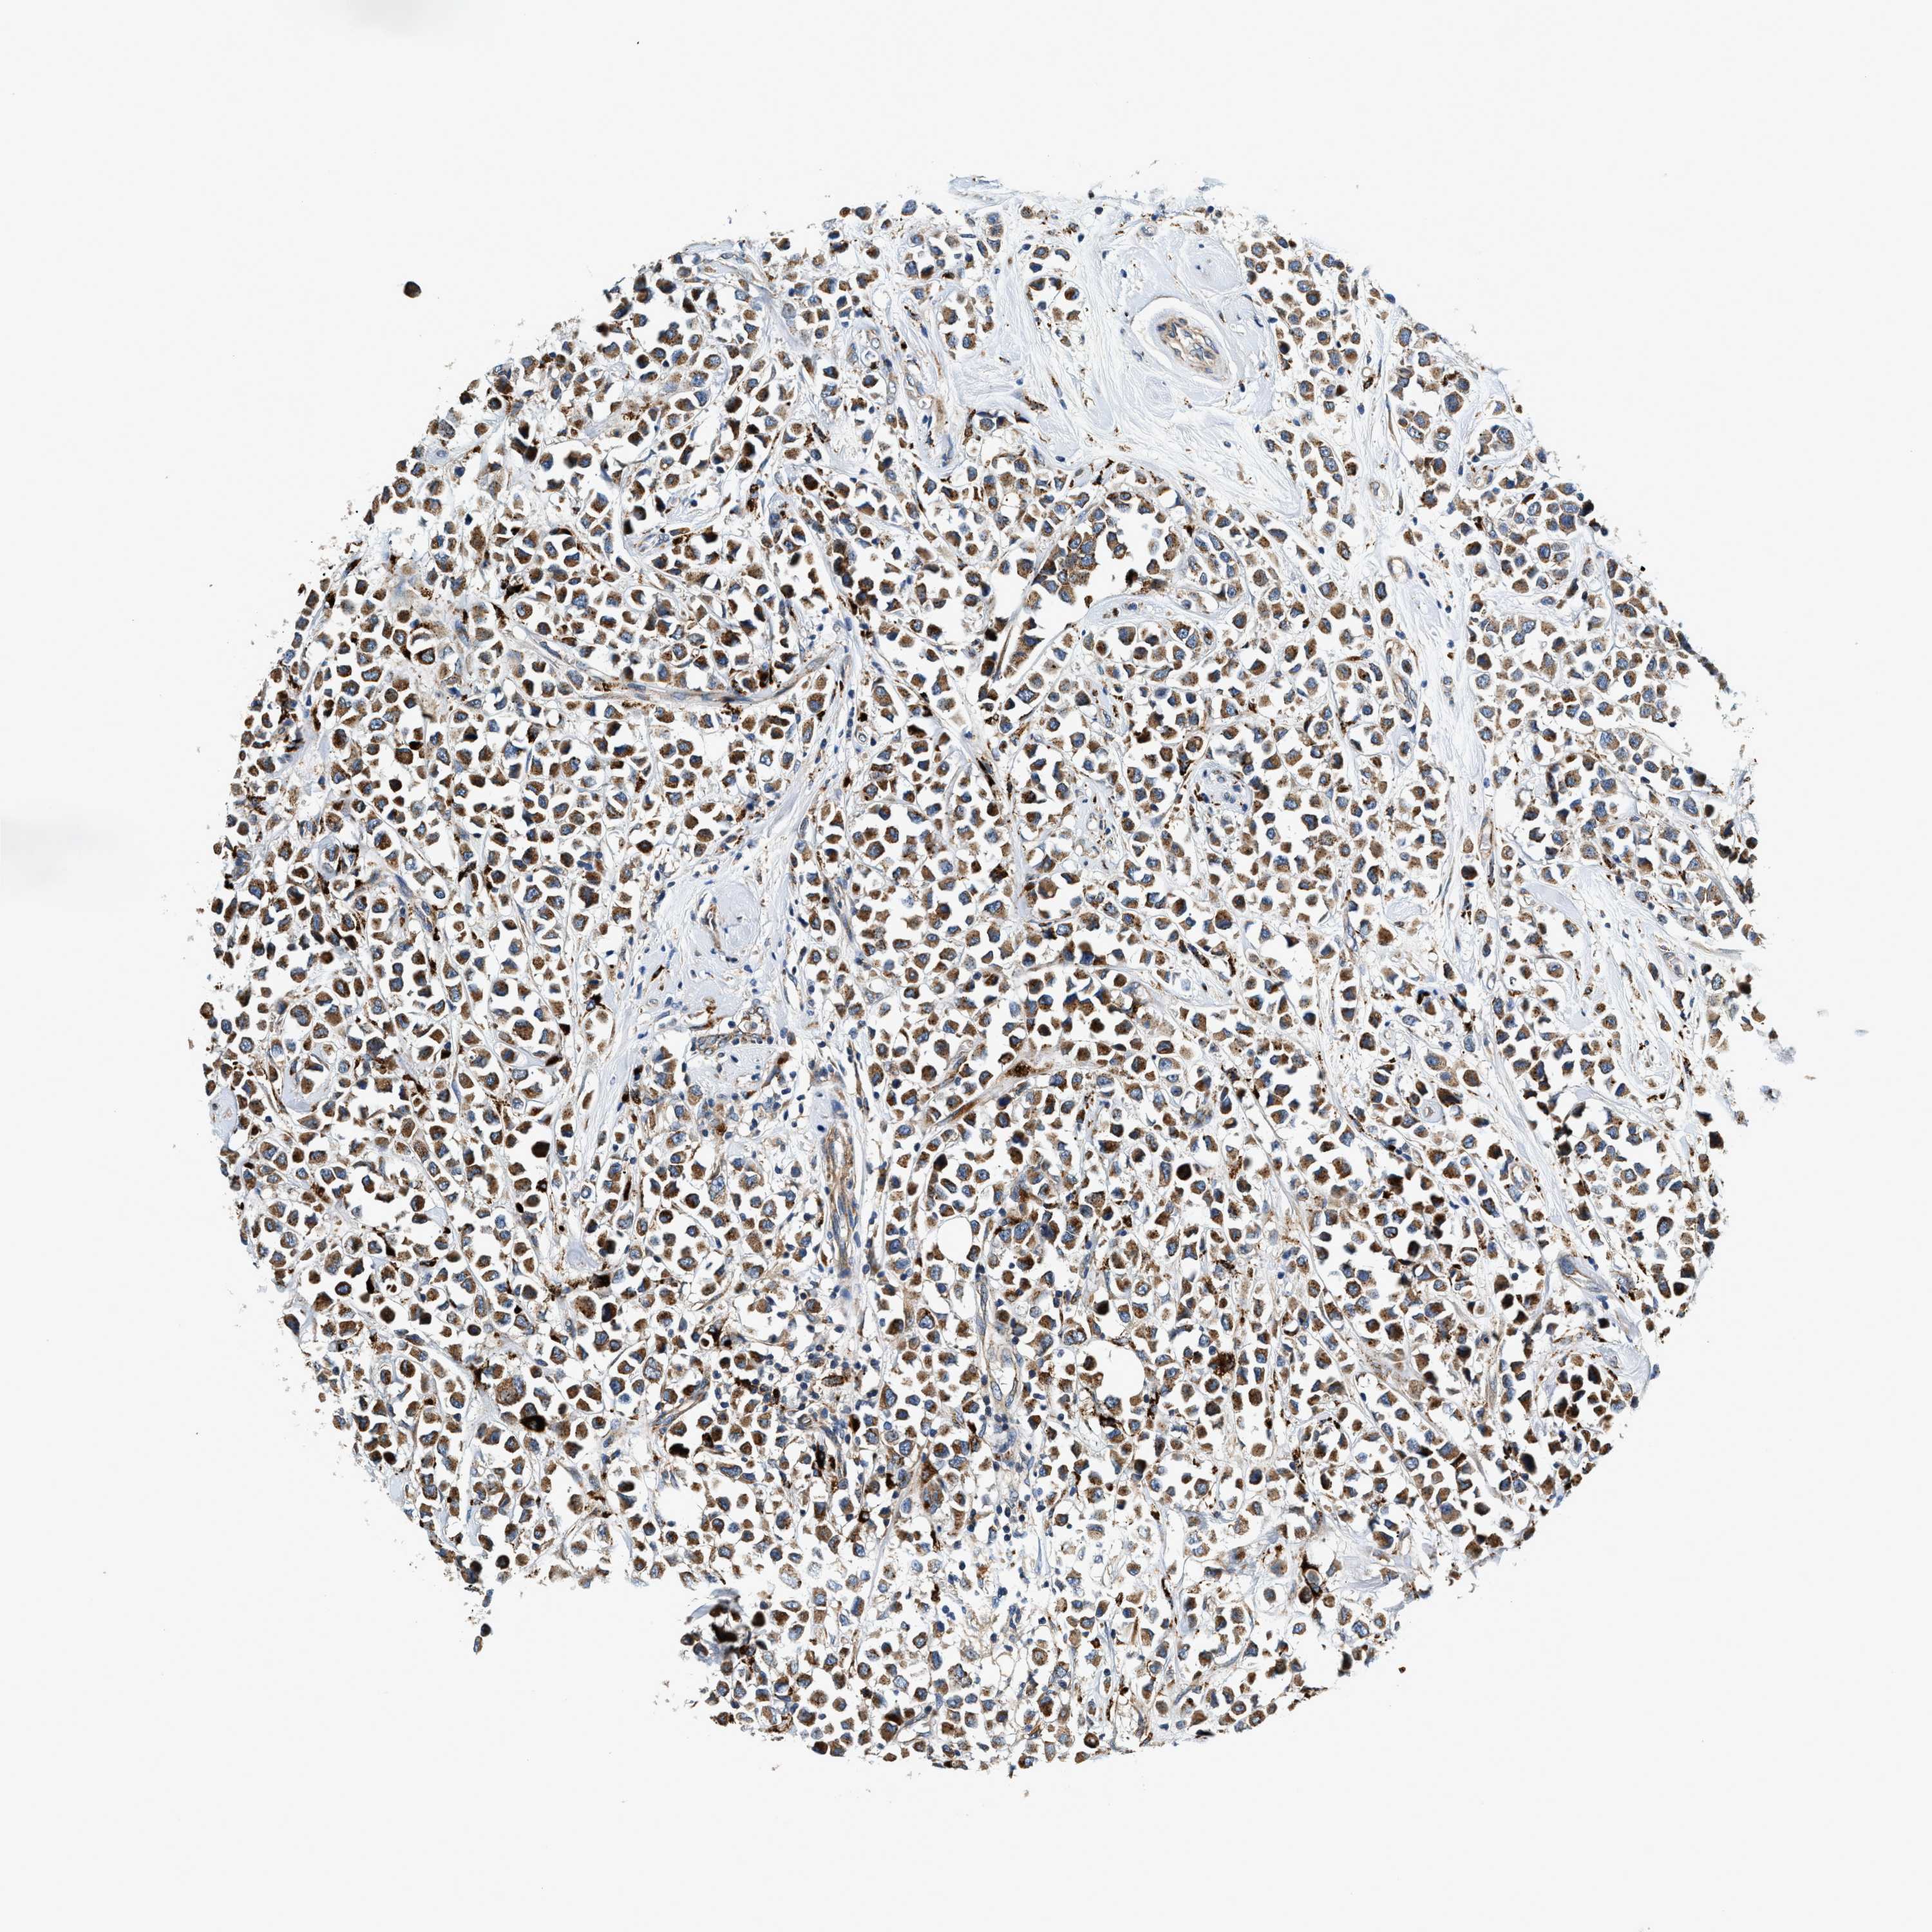

CANCER BREAST CANCER Show tissue menu

BRCA TCGA BRCA VALIDATION PROTEIN EXPRESSION